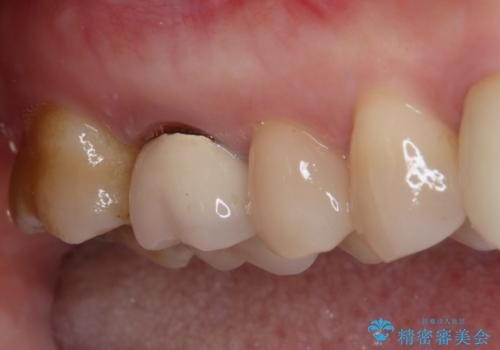

- 眠れないほどの激痛で、噛むと涙が出るほど痛むとのことで来院された患者様です。

咬合力が極めて強く、診査の結果、強大な咬合力により歯内の神経組織が炎症を起こしていることが予想されました。

神経組織は失活しておらず、冷たいもの対する痛みはそれほど強いものではなかったので、場合によっては歯が破折しており、抜歯が必要となる可能性が示唆されました。

患者様と相談し、まずは神経組織を取り除く前提で処置を開始し、その過程で歯の破折が認められた場合には抜歯することとしました。

残念ながら歯冠から歯根に向かって破折が認められたため、患者様了解のもと、抜歯してインプラントの即時埋入を行いました。